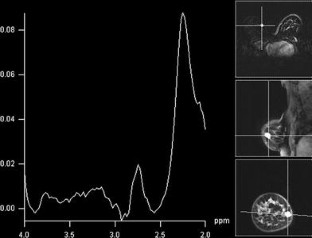

Dermatofibrosarcoma protuberans (DFSP) of the breast is a rare malignant tumor, and its preoperative diagnosis is extremely difficult. Local recurrence of DFSP is frequent after incomplete resection because of either false diagnosis or inadequate standard surgical excision. We present a case of DFSP that showed disconcordant results using different imaging modalities, suggesting that the MRI finding of subcutaneously located highly vascular tumor with suspicious kinetics but together with negative Cho peak on (1H) MRS, might be suggestive of the diagnosis of DFSP.